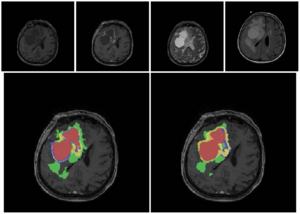

- 4.27 Multi-Modal Glioblastoma Segmentation: Man versus Machine

- 4.28 Rapid Amygdala Responses during Trace Fear Conditioning without Awareness